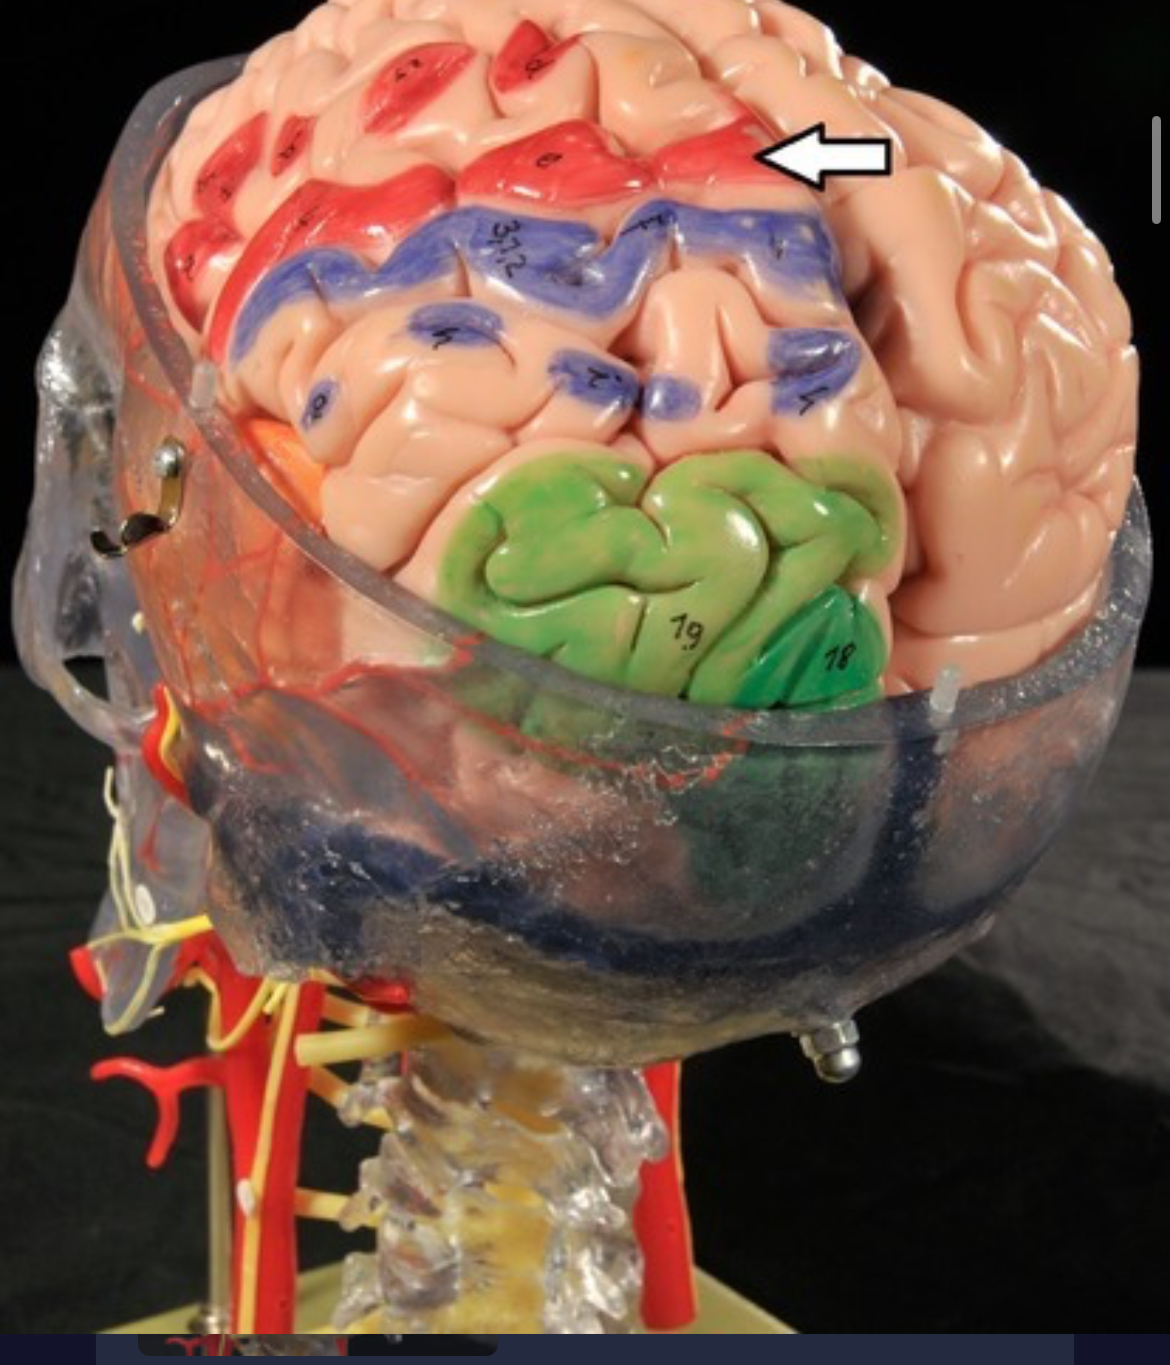

Precentral gyrus

Postcentral gyrus

Central sulcus